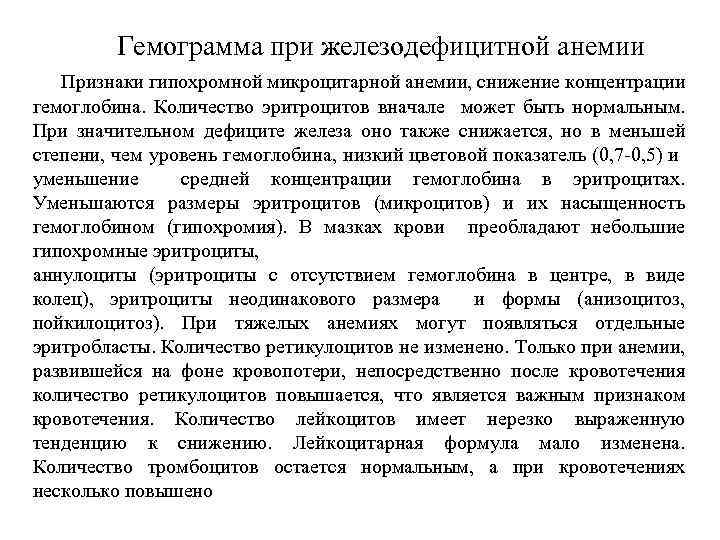

Гемограмма при железодефицитной анемии Признаки гипохромной микроцитарной анемии, снижение концентрации гемоглобина. Количество эритроцитов вначале может быть нормальным. При значительном дефиците железа оно также снижается, но в меньшей степени, чем уровень гемоглобина, низкий цветовой показатель (0, 7 -0, 5) и уменьшение средней концентрации гемоглобина в эритроцитах. Уменьшаются размеры эритроцитов (микроцитов) и их насыщенность гемоглобином (гипохромия). В мазках крови преобладают небольшие гипохромные эритроциты, аннулоциты (эритроциты с отсутствием гемоглобина в центре, в виде колец), эритроциты неодинакового размера и формы (анизоцитоз, пойкилоцитоз). При тяжелых анемиях могут появляться отдельные эритробласты. Количество ретикулоцитов не изменено. Только при анемии, развившейся на фоне кровопотери, непосредственно после кровотечения количество ретикулоцитов повышается, что является важным признаком кровотечения. Количество лейкоцитов имеет нерезко выраженную тенденцию к снижению. Лейкоцитарная формула мало изменена. Количество тромбоцитов остается нормальным, а при кровотечениях несколько повышено

Пример гемограммы при железодефицитной анемии Эритроциты – 1. 1. 10. 12/л, Нв - 87 г/л, ЦП - 0. 55, Лейкоциты - 2. 10. 9/л, п/я - 2%, с/я - 67%, лимф - 30%, м - 1%, СОЭ 34 мм/час Тромбоциты – 200. 10. 9/л Эритроциты – 2. 2. 10. 12/л, Нв - 74 г/л, ЦП - 0. 65, Лейкоциты - 4. 10. 9/л, ретикулоциты 1%, п/я - 2%, с/я - 66%, лимф - 30%, м - 1%, СОЭ 34 мм/час